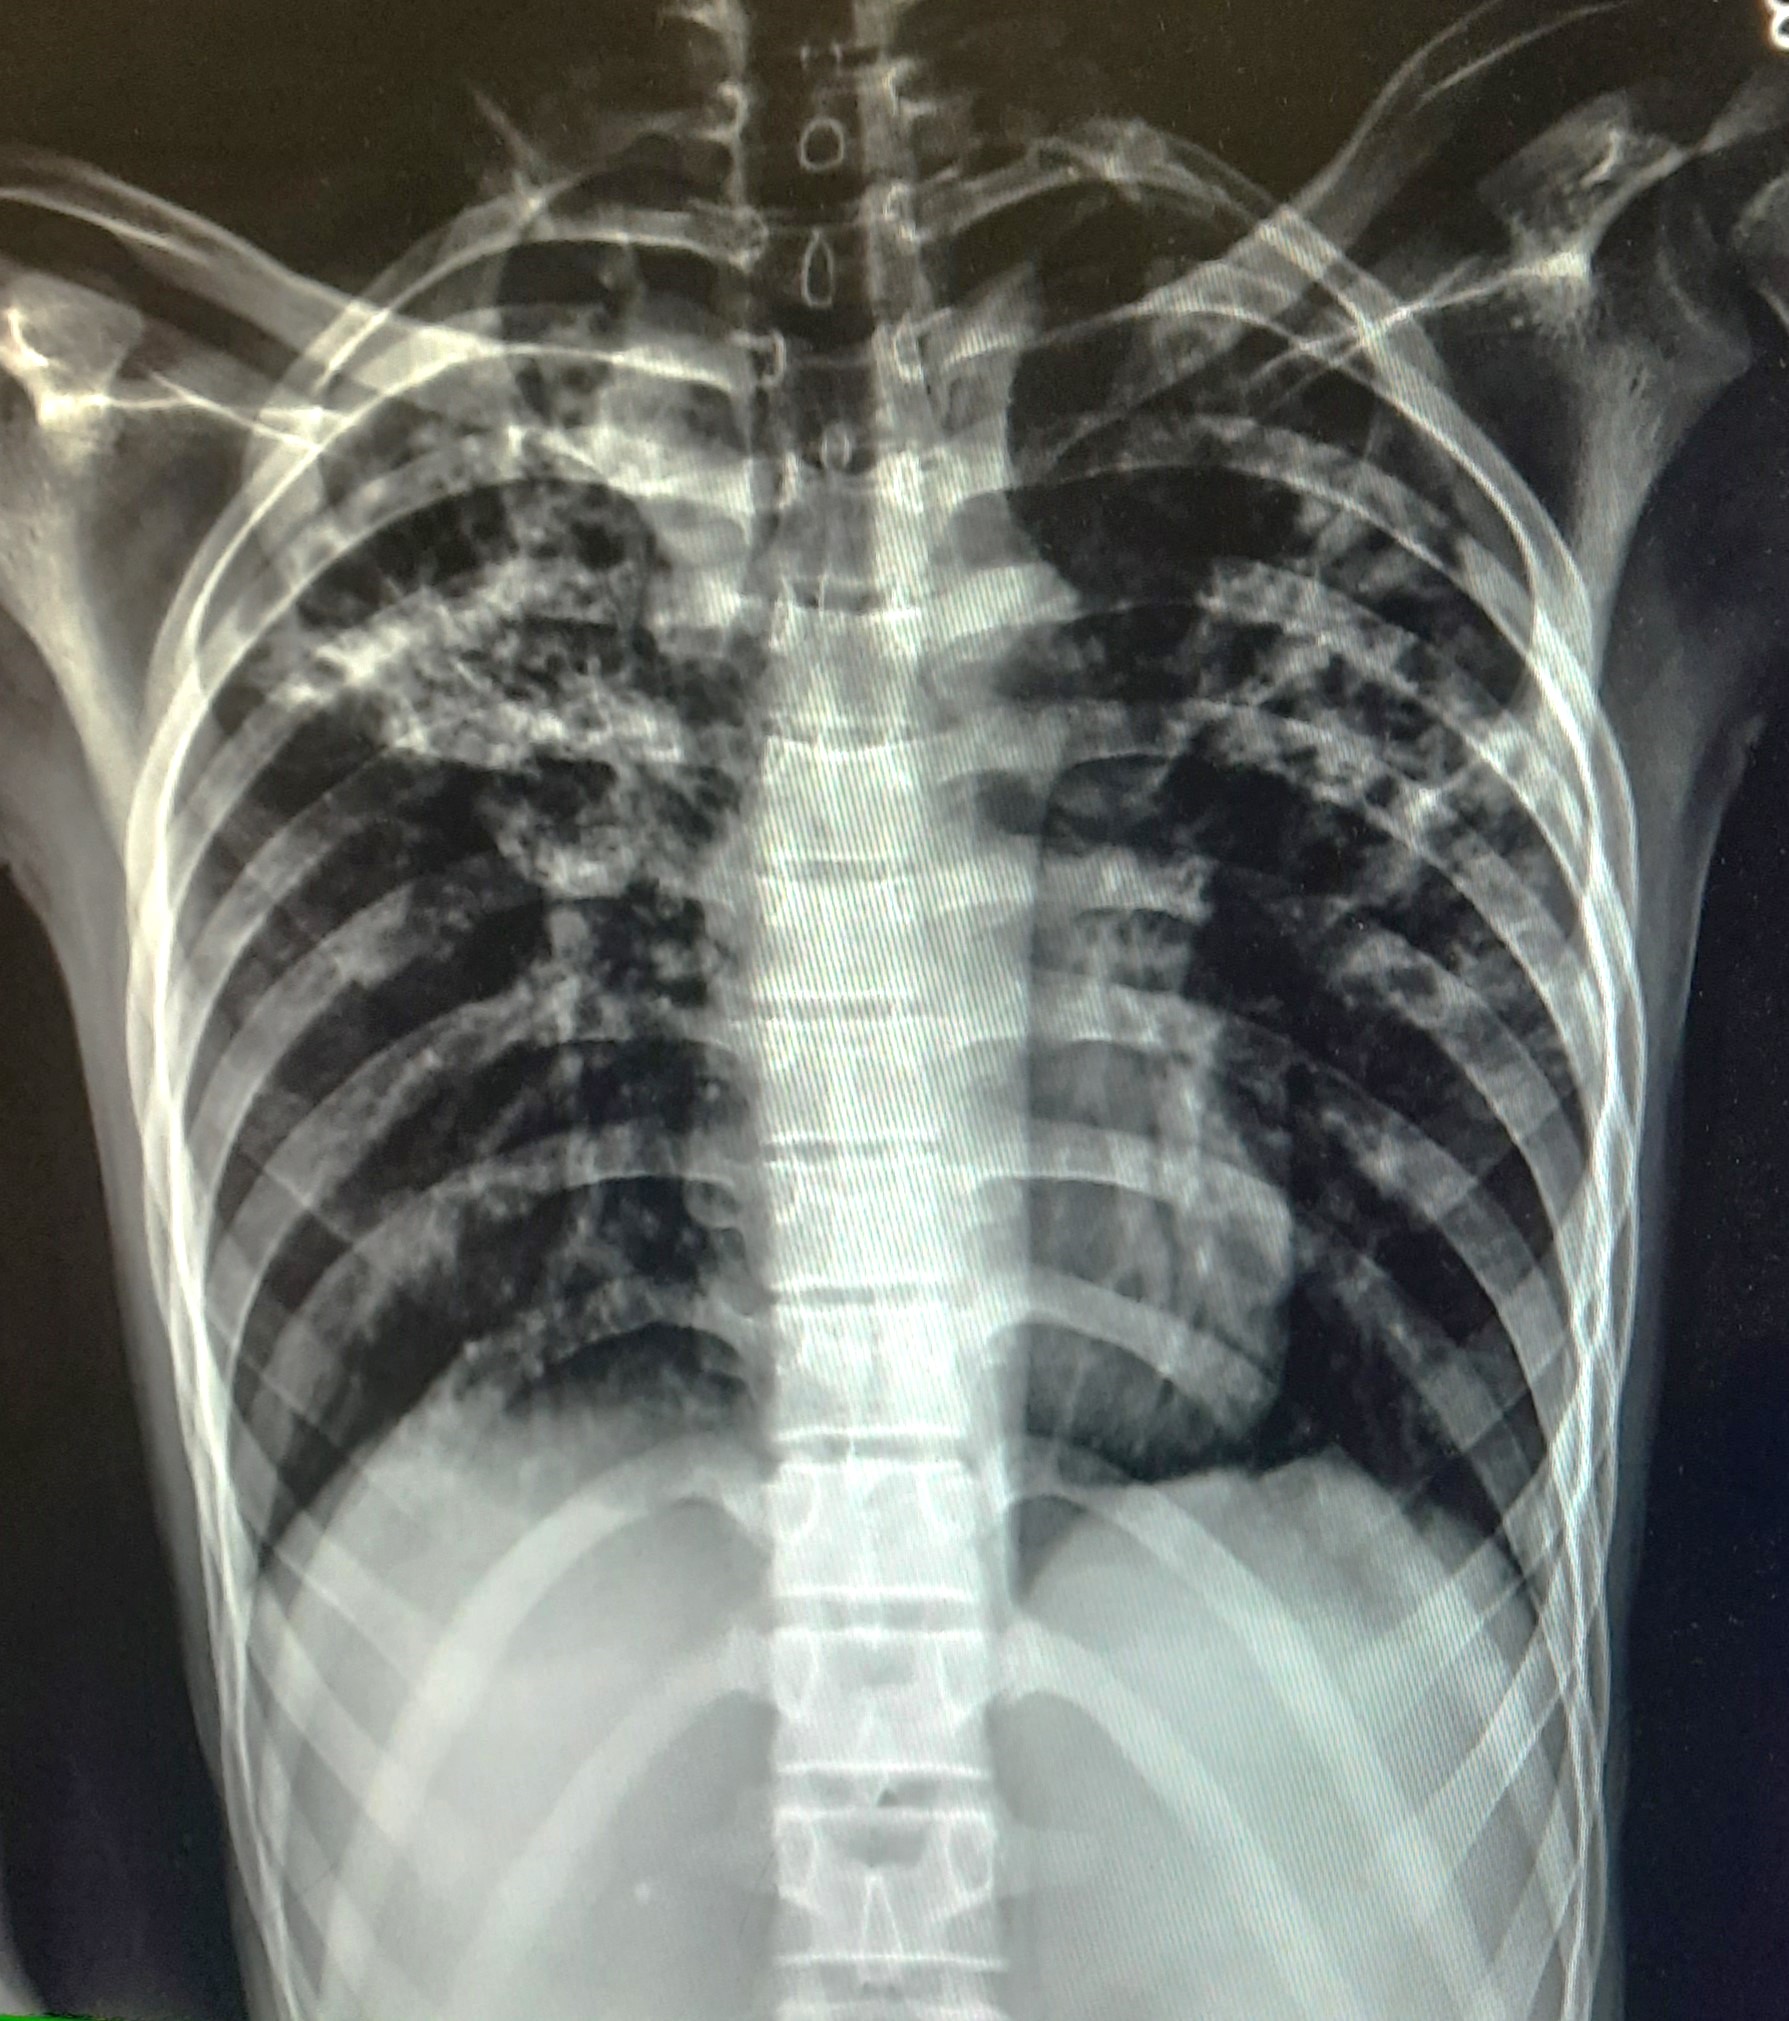

| 51 | IGGMC, Nagpur, Nagpur | P2 | 29-4421 | Santosh Neware | Consent taken on Paper | 40 Yrs. |

Provisional Diag : Pulmonary Tuberculosis

Final Diag : Pulmonary tuberculosis (Microbiologically Confirmed PTB) |

TB Case (Confirmed) | Right Upper & mid zone fibro cavitary lesion present, upward pull of right hemidiaphragm, tracheal pull right sided | Abnormality visible on x-ray |